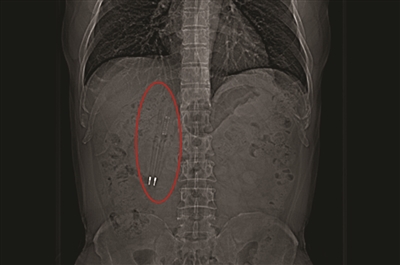

CT中能清晰看到亮闪闪的笔尖。

家住昆山的王先生,今年50岁,今年2月份,他去昆山中医院体检时心头一紧,因为体检结果显示,他的十二指肠部位有明显异物。其后,王先生赶紧做了个CT,医生发现,王先生的十二指肠里竟有两个笔状的异物。

王先生体内的笔长约12厘米,位于十二指肠球降部。昆山中医院消化内科主任徐宏伟介绍说,这个笔从口中吞下,经过了食管、胃、幽门,到达了十二指肠,其中有一支笔的笔尖已经戳到了肠壁,由于十二指肠长度和一支笔的长度差不多,笔无法再向下滑。

王先生吞下去的这两支笔都是塑料的,从CT上看,还可以看到笔里的金属弹簧和金属笔尖在闪闪发光。

笔藏在肠道里长达36年未被发现,这是为什么呢?徐宏伟感慨道:“他真的是非常幸运。”因为,两支笔被吞下后,平行地进入了食管,进入到十二指肠后,也是一直跟肠道平行,因此,未对其身体造成很大的伤害。